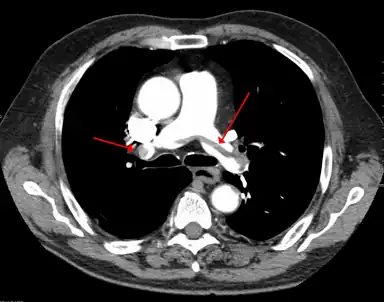

A pulmonary embolism (PE) occurs when a blood clot from a deep vein (a DVT) detaches from a vein (embolizes), travels through the right side of the heart, and becomes lodged as an embolus in a pulmonary artery that supplies deoxygenated blood to the lungs for oxygenation.[28] Up to one-fourth of PE cases are thought to result in sudden death.[12] When not fatal, PE can cause symptoms such as sudden onset shortness of breath or chest pain, coughing up blood (hemoptysis), and fainting (syncope).[29][30] The chest pain can be pleuritic (worsened by deep breaths)[29] and can vary based upon where the embolus is lodged in the lungs. An estimated 30–50% of those with PE have detectable DVT by compression ultrasound.[30]

Thrombolysis is the injection of an enzyme into the veins to dissolve blood clots, and while this treatment has been proven effective against the life-threatening emergency clots of stroke and heart attacks, randomized controlled trials[139][140][141] have not established a net benefit in those with acute proximal DVT.[5][142] Drawbacks of catheter-directed thrombolysis (the preferred method of administering the clot-busting enzyme[5]) include a risk of bleeding, complexity,[lower-alpha 12] and the cost of the procedure.[125] Although, while anticoagulation is the preferred treatment for DVT,[125] thrombolysis is a treatment option for those with the severe DVT form of phlegmasia cerula dorens (bottom left image) and in some younger patients with DVT affecting the iliac and common femoral veins.[12] Of note, a variety of contraindications to thrombolysis exist.[125] In 2020, NICE kept their 2012 recommendations that catheter-directed thrombolysis should be considered in those with iliofemoral DVT who have "symptoms lasting less than 14 days, good functional status, a life expectancy of 1 year or more, and a low risk of bleeding."[138]